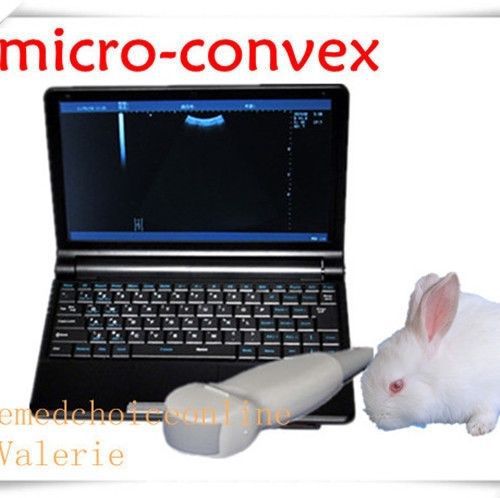

Vet Veterinary Ultrasound Scanner/Machine w Micro-convex probe opt rectal Animal

Vet Veterinary Ultrasound Scanner/Machine&Micro-convex probe opti rectal Animals

VET Digital Laptop Ultrasound Scanner Machine+Microconvex Probe Amimal BIG SALE

VET Digital Laptop Ultrasound Scanner Machine+Microconvex Probe f little Amimal